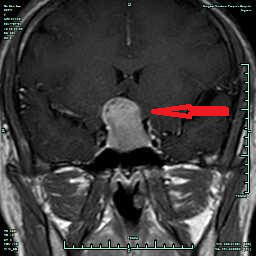

CASE2 病人***女性,46岁,因“视物明显下降2周”入院,入院诊断:垂体侵袭性大腺瘤;

在全麻下行经鼻内镜下垂体瘤切除,术后视力较前明显好转,术后恢复良好, 术后8天出院,出院3月复查仅海绵窦区少许肿瘤残留,继续随访。(红箭头提示垂体大腺瘤,蓝箭头提示术后复查海绵窦有少许肿瘤残留)